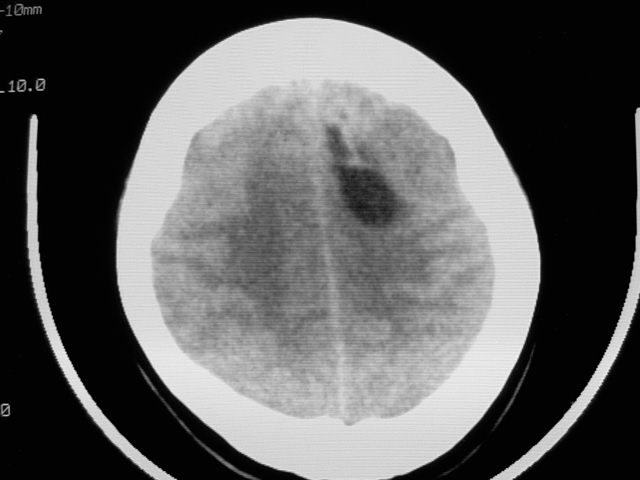

f39y,头疼、眩晕。患者拒绝强化。

左侧脑室增大,前角明显,中线向右移位,左侧脑室内见一肿块,密度不均,1室管膜瘤?2脑囊虫?

左额叶见一巨大椭圆形略低、低密度混杂密度肿块,边界清楚,似与侧脑室额角相通,明显占位效应,左侧侧脑室受压变形,右侧侧脑室扩大,中线结构向右明显弧形移位。鞍上池闭塞。

考虑:1、左额叶良性占位性病变,以皮样囊肿可能性大,伴镰下疝。

左侧脑室增大,前角明显,中线向右移位,左侧脑室内见一肿块,密度不均,内见钙化,1室管膜瘤?2脑囊虫?

类圆形低密度病灶与脑室内密度明显有差别,考虑:低密度病灶压迫四脑室形成的特殊影像。支持:皮样囊肿。

感觉病灶位于侧脑室前角内,而体部受压,病灶形态同前角一致,右侧脑室前角变形并不太严重,病灶呈混杂密度,考虑皮样囊肿或室管膜瘤可能性大一些。